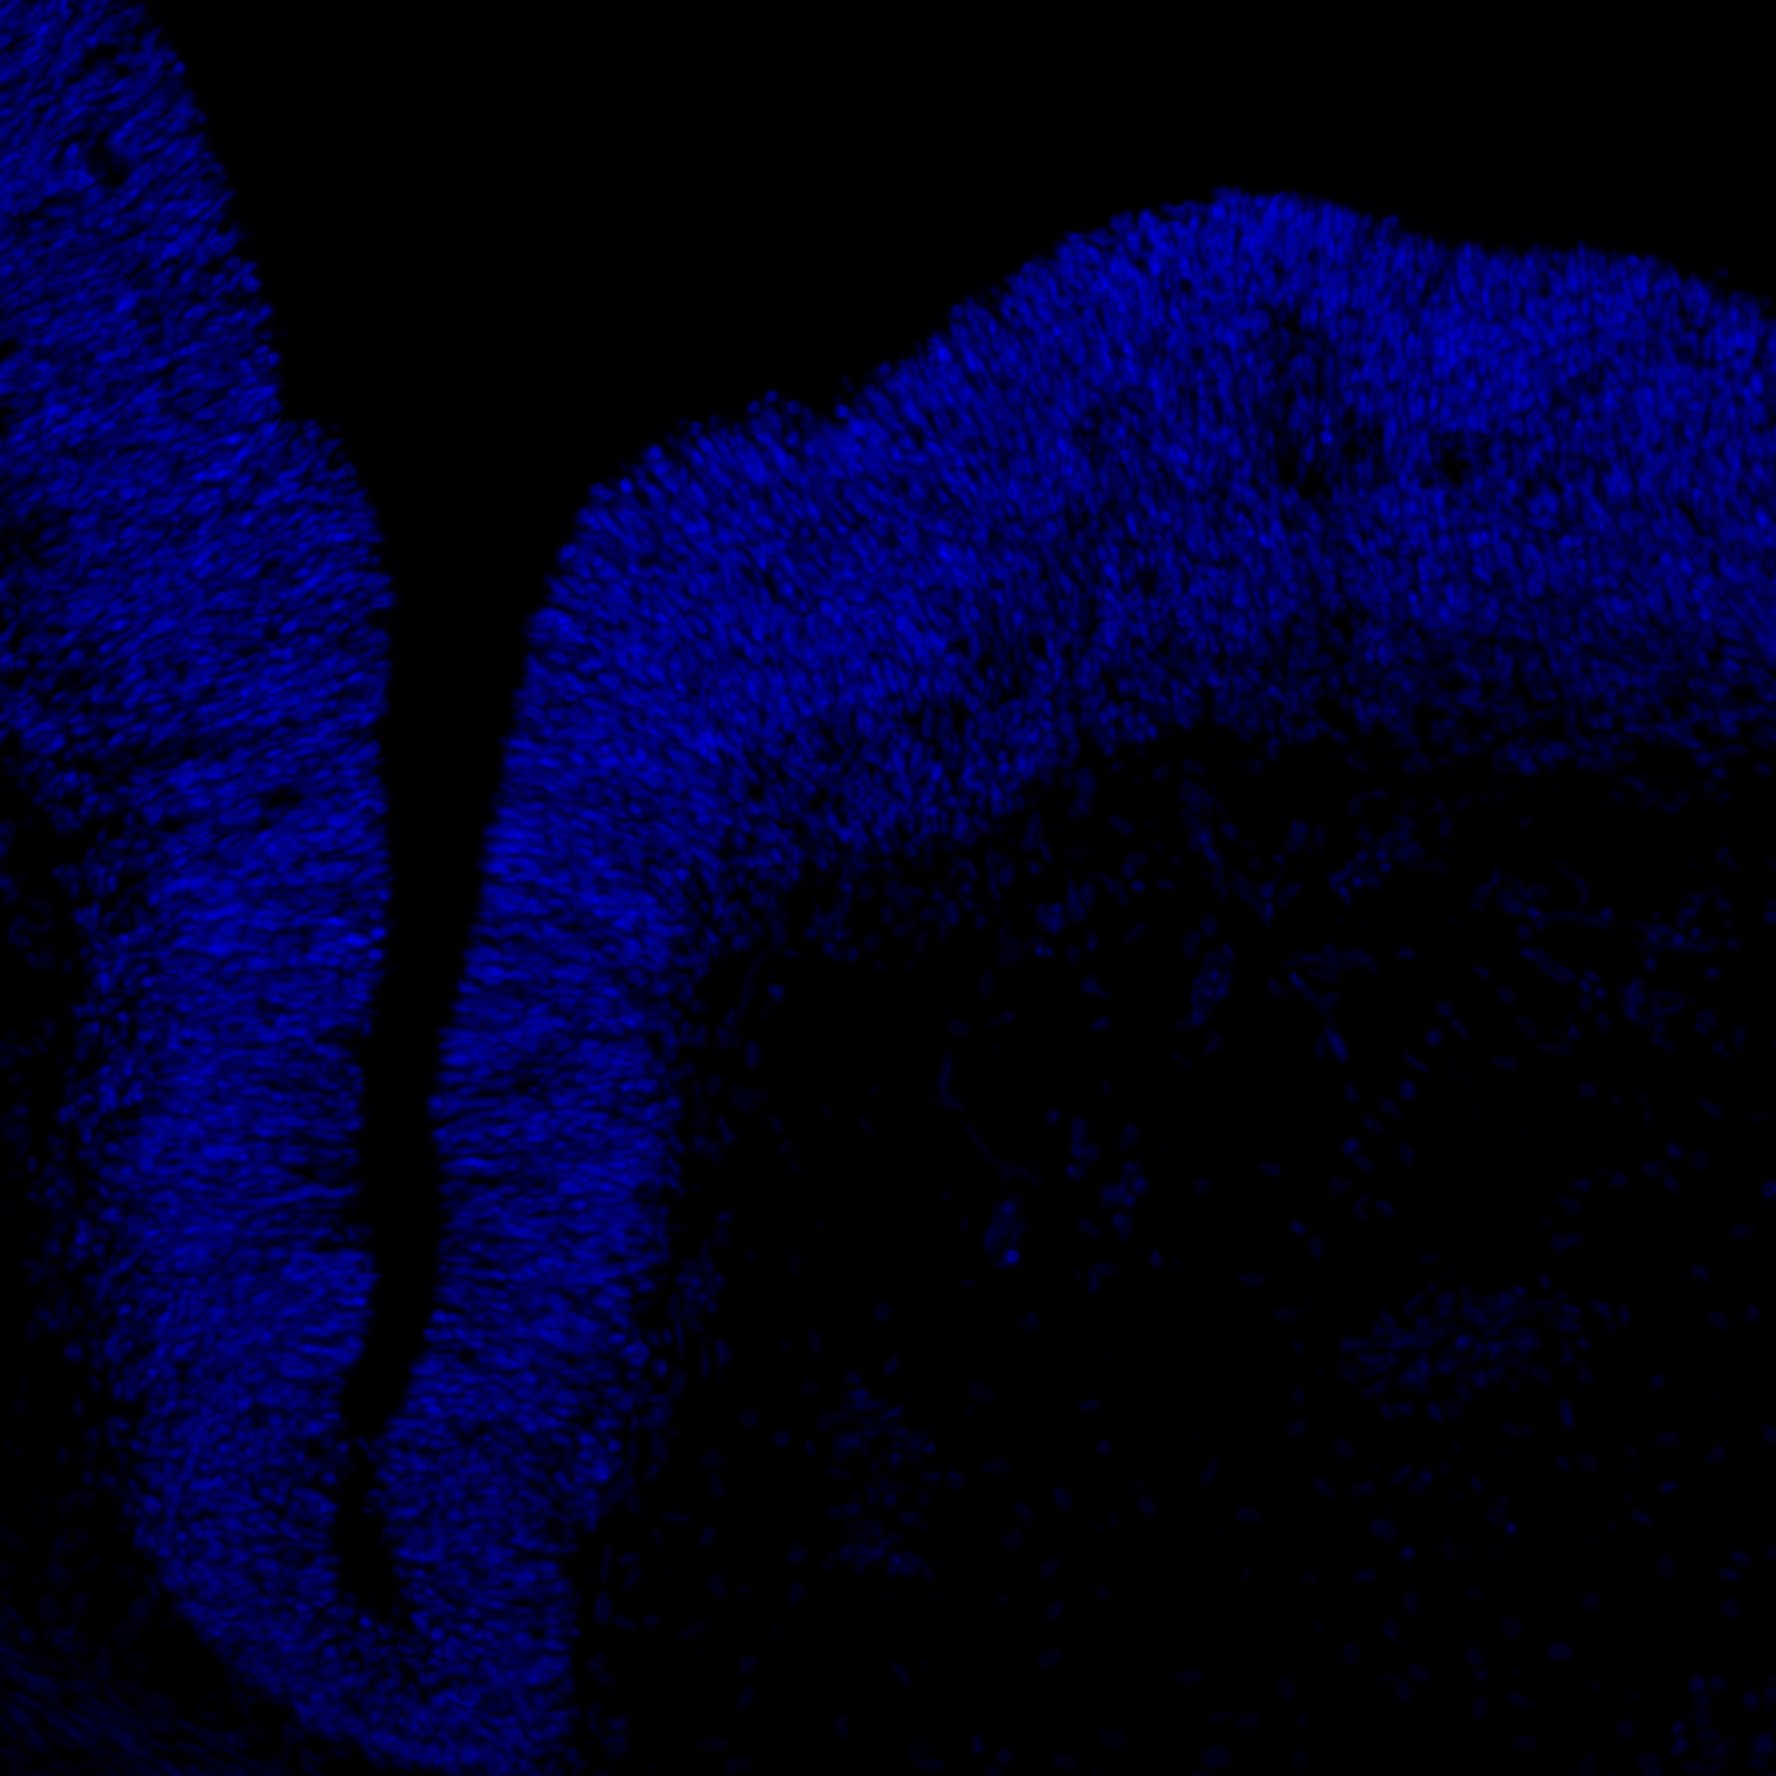

An anatomical analysis of the developing human midbrain from 6 post-conceptional weeks (PCW) to 22 PCW reveals increased tissue complexity, characterized by the emergence of dopaminergic nuclei, as highlighted by immunofluorescence analysis for tyrosine hydroxylase (TH).

DAPI

11PCW human midbrain

MAP2